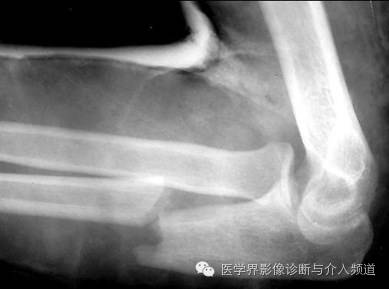

15、Essex Lopresti 骨折:

桡骨小头粉碎性骨折,伴下桡尺关节脱位。多有高处坠下造成。